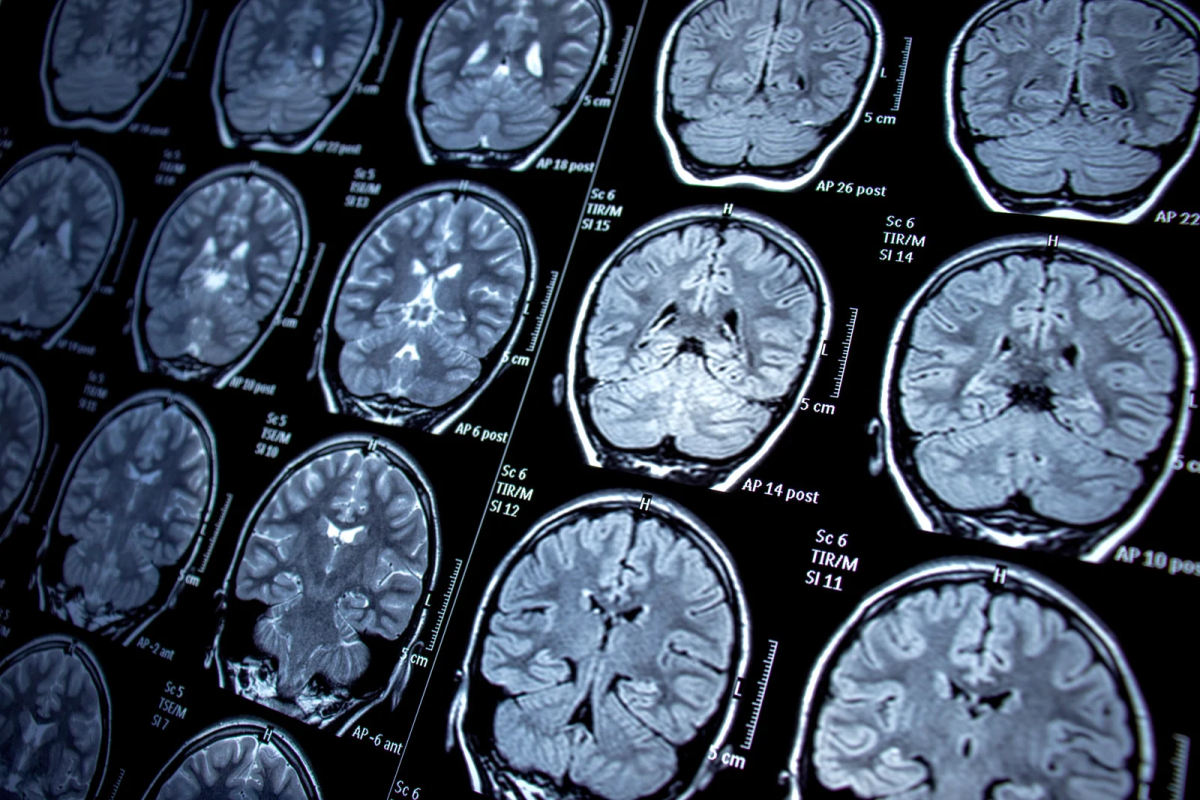

Epilepsija je kronični neurološki poremećaj obilježen ponavljanim epileptičkim napadajima koji nastaju zbog poremećene električne aktivnosti u mozgu. Pogađa ljude svih dobnih skupina.

Važno je naglasiti: nije svaki napadaj epilepsija. Slični simptomi mogu se javiti zbog naglog pada šećera u krvi, srčanih poremećaja ili psihičke traume. Zato je pravilna dijagnoza ključna i postavlja se na temelju detaljne anamneze, neurološkog pregleda i EEG snimanja.